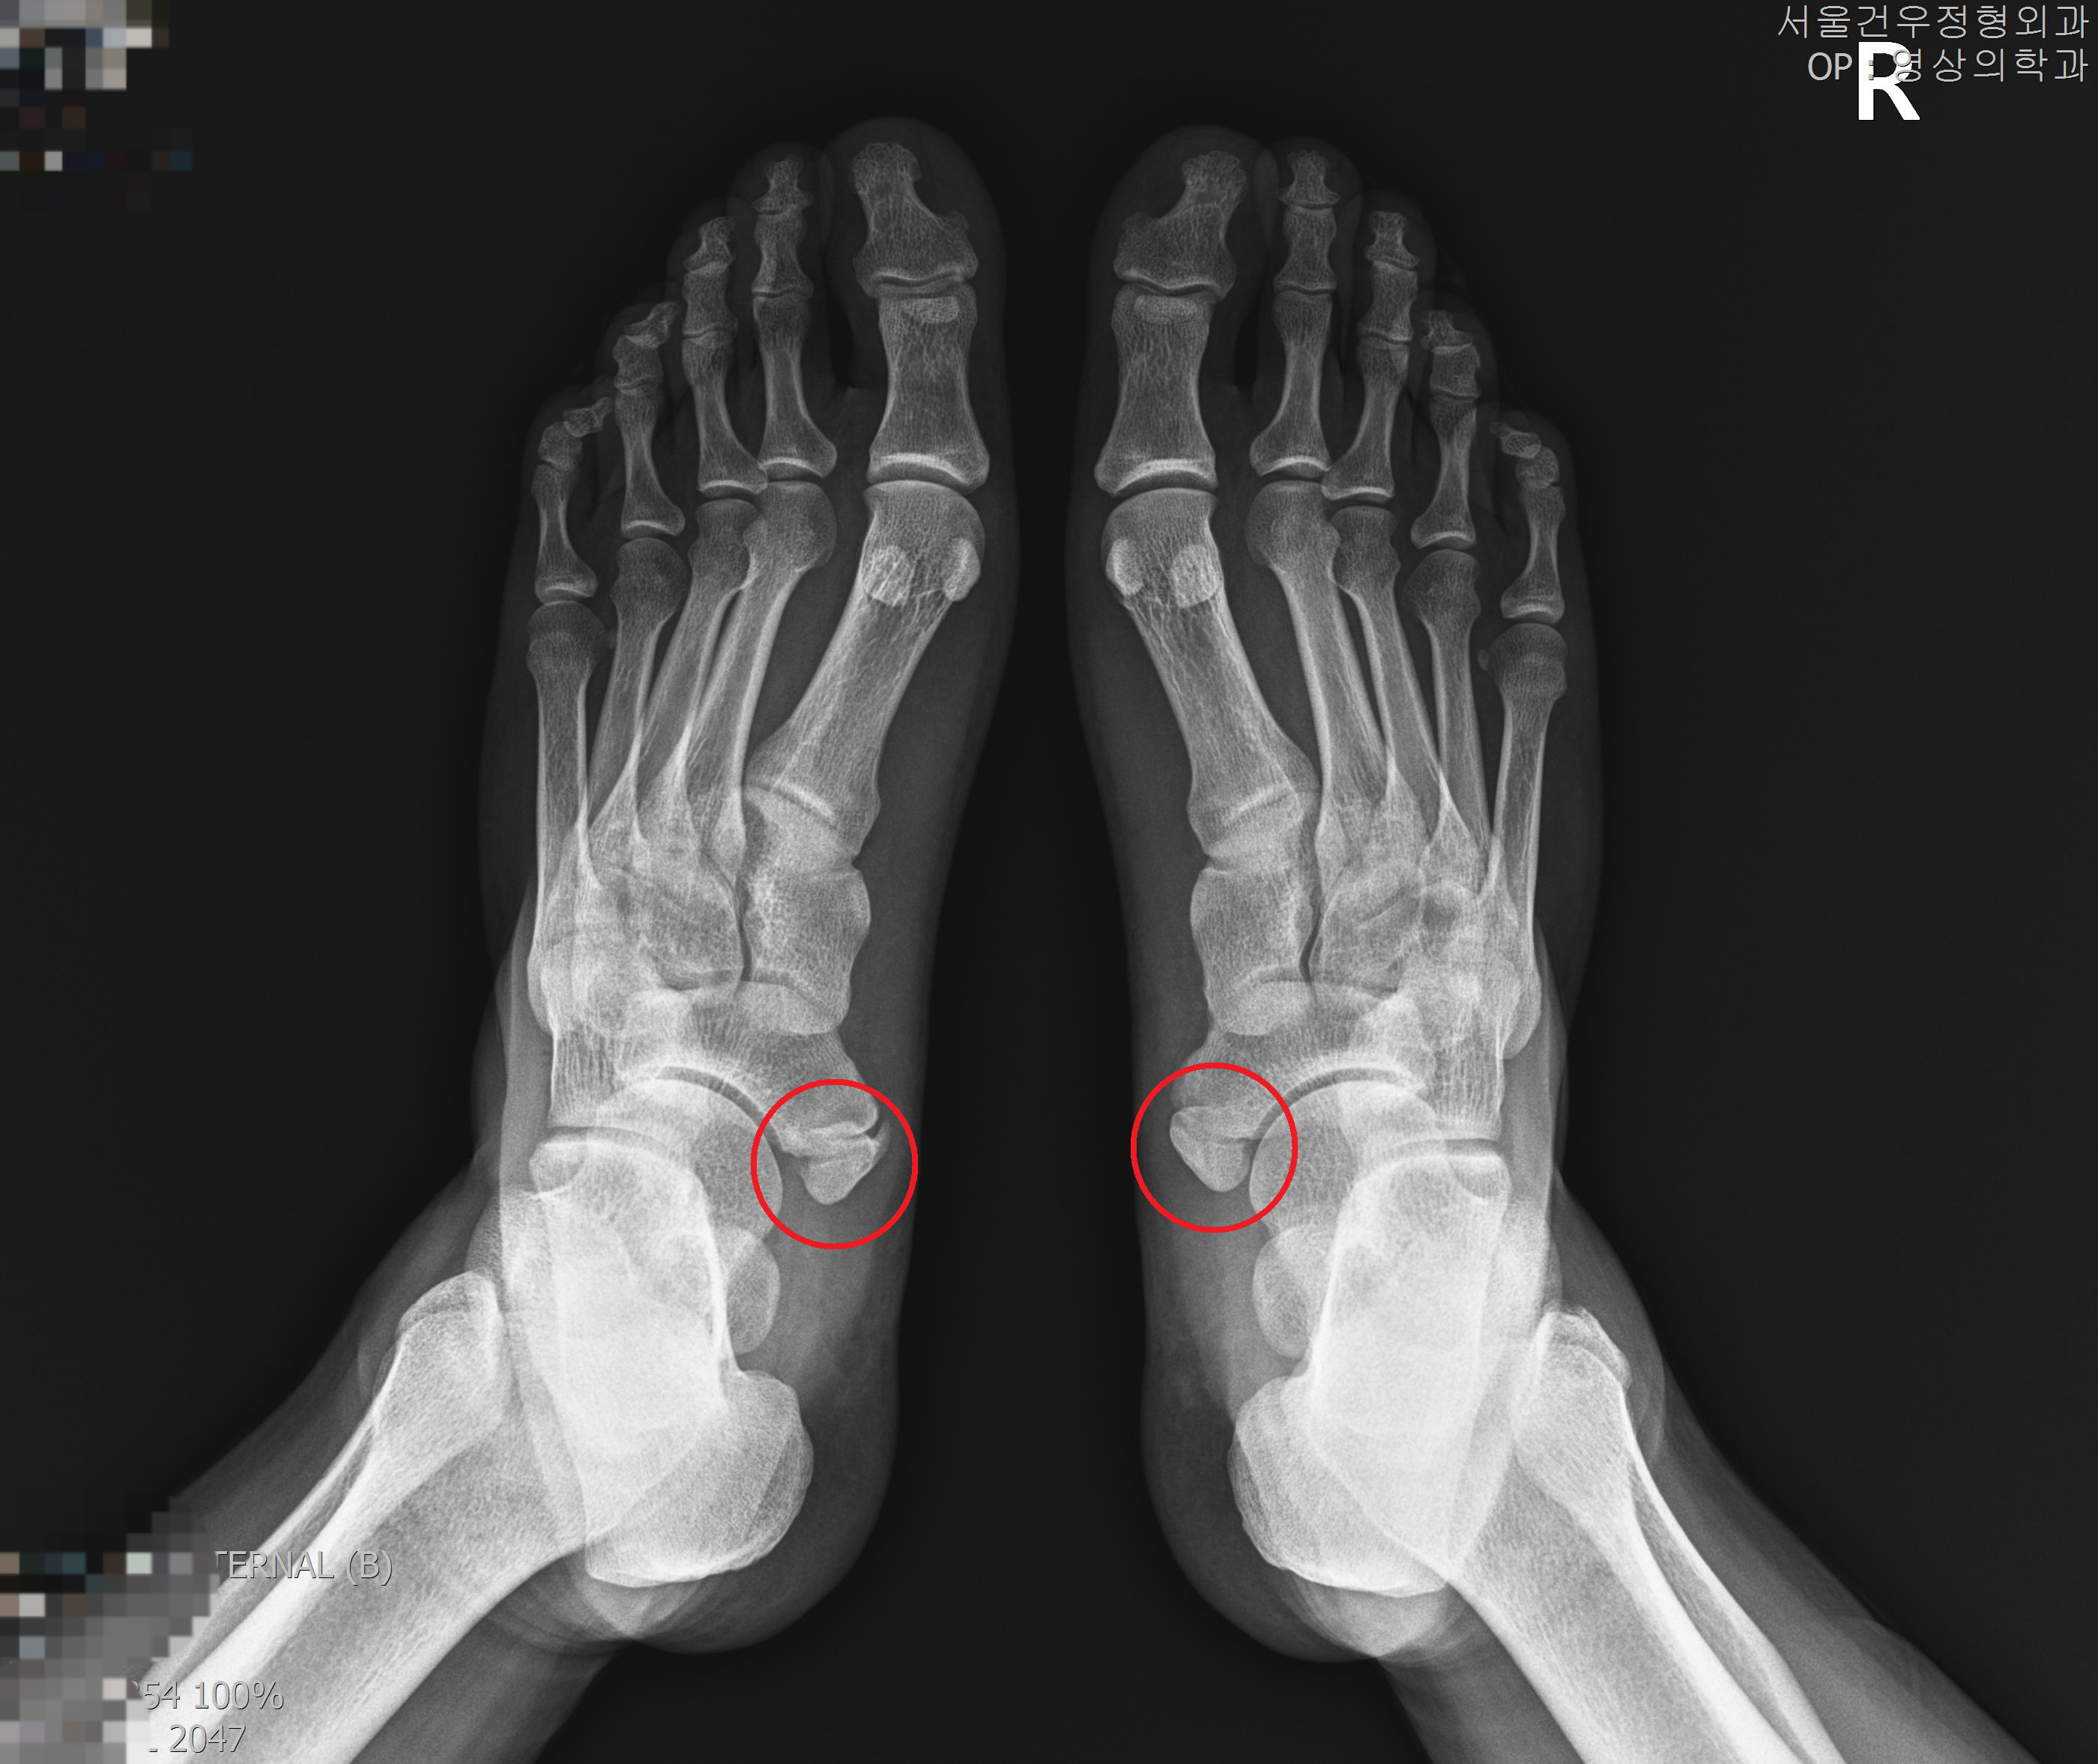

부주상골평발 동반된 경우 치료 방법은? 부주상골평발은 발에 생기는 흔한 문제 중 하나입니다. 통계에 따르면 부주상골평발은 적게는 10%, 많게는 40% 정도의

부주상골증후군치료: 수술적 vs. 비수술적 치료방법 부주상골증후군은 발생 원인에 따라 다양한 증상을 유발할 수 있는 흔한 질병 중 하나입니다. 이 질병은

부주상골증후군통증 여부에 따라 치료가 달라지는 이유 부주상골증후군은 손목에 있는 한 쌍의 뼈 중 하나인 부주상골의 염증이나 손목의 뼈들 사이의 연골